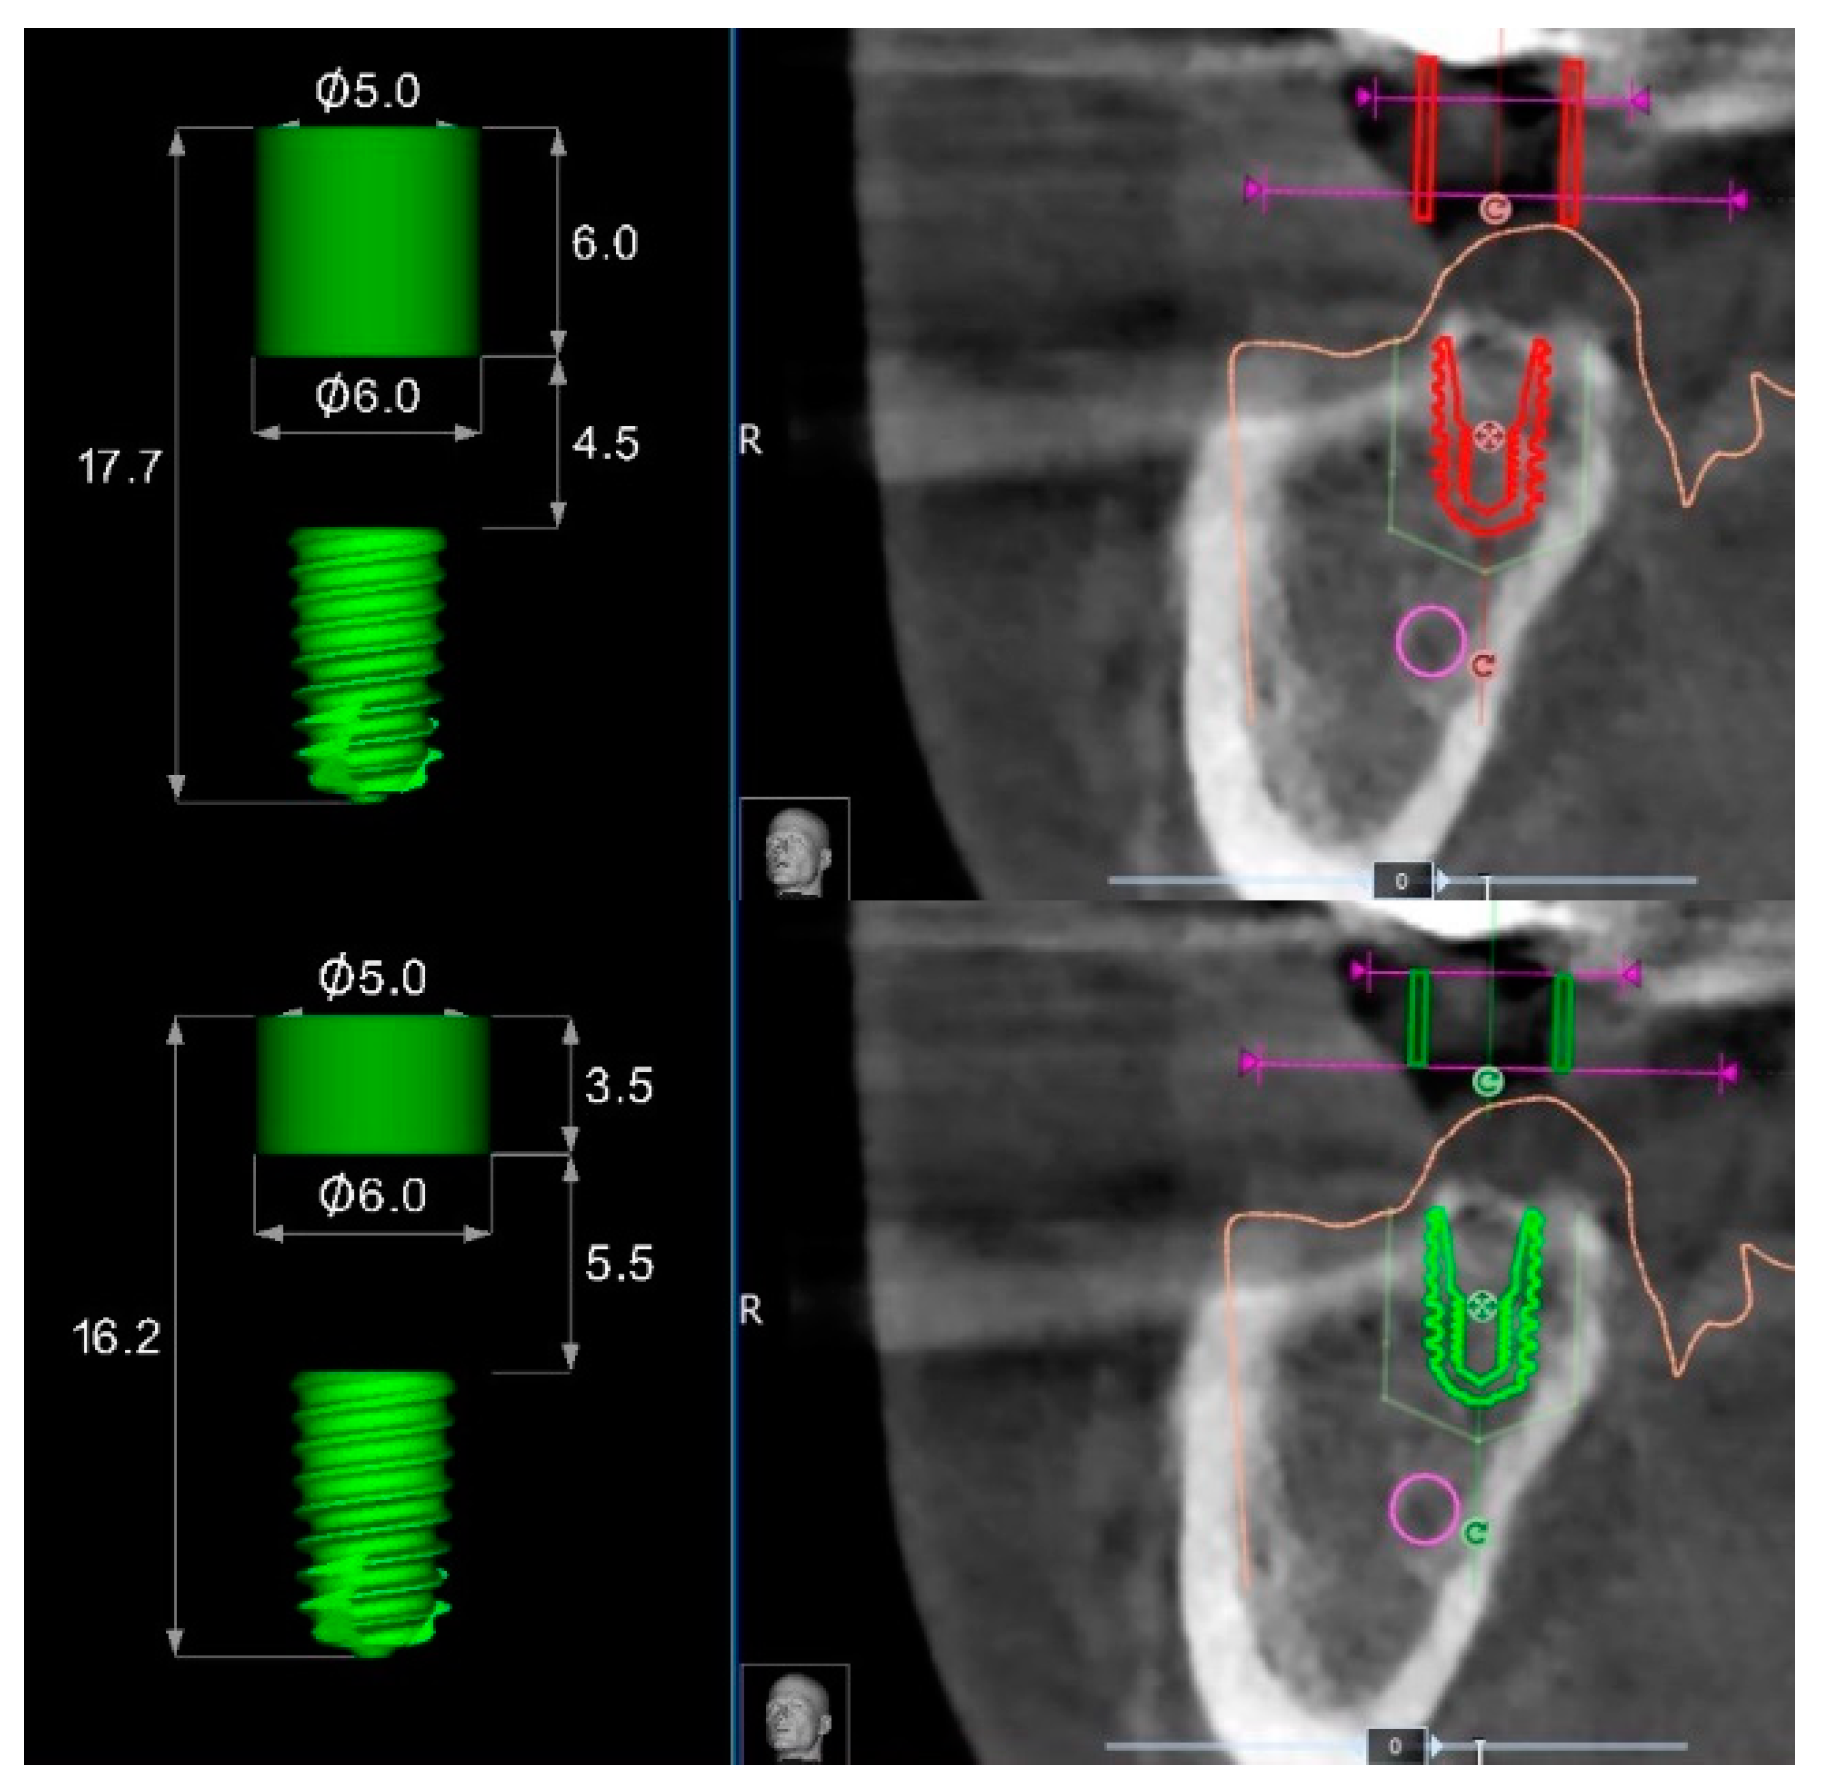

Accordingly, in the templates without metallic sleeves, the contact points between the template and the surgical drills with the entire space between the soft tissue and the templets results in a longer guide compared to the 3.5 mm of standard metallic sleeves, plus 1 mm of the metallic reduction (Figure 8) in case of templates with metallic sleeves. This difference should allow for larger and more stable contact between the surgical template and the guided drills during the implant site development, slightly reducing the overall wobbling of the guided drills. Indeed, a longer guiding channel was found to reduce the angular deviations of implants in an in vitro investigation [9]. Lastly, the implant mount drivers used in combination with surgical templates designed without metallic sleeves (NoMount Driver and Fixture Driver, OneGuide Kit, Osstem) are designed without any stop drill to the surgical guide. A stop drill should touch the surgical template on the side, creating a high pressure on the template that could generate a distortion of the same template, resulting in a reduction of the final implant accuracy [7]. Another benefit of the surgical templates designed without metallic sleeves was the reduced mesio-distal space. In fact, the metallic tubes have a thickness of 0.5 mm, which could make it impossible for their use in the case of narrow mesio-distal distance, such as in case of lower incisor or upper lateral incisors. In this case, the manual insertion of the implant after removing the surgical template is required.

Figure 8.

Differences between surgical templates with (lower) and without (upper) metallic sleeves for a regular diameter implant of 7 mm length.